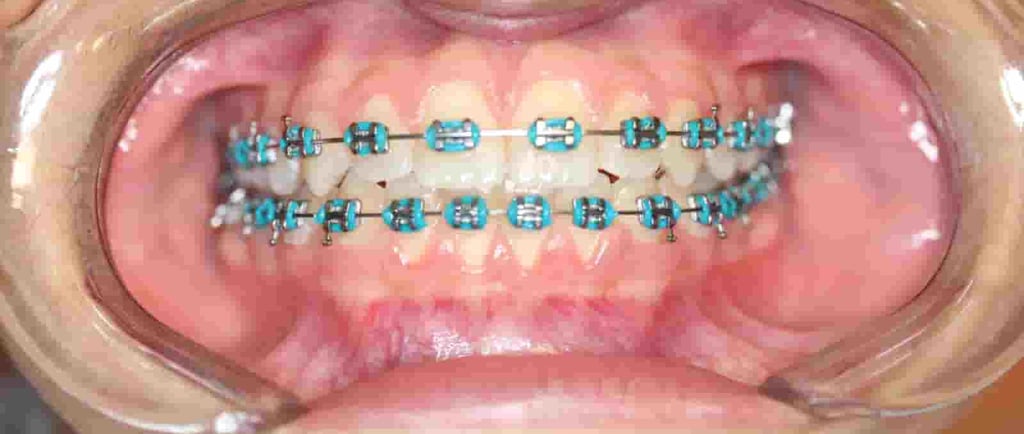

Los brackets y alambres crean rincones donde se acumulan restos de comida y placa bacteriana con facilidad. Si no se limpian bien, pueden aparecer caries, encías inflamadas o esas manchitas blancas alrededor del bracket que arruinan el “antes y después”.

Manchas blancas (desmineralización del esmalte) alrededor de los Brackets